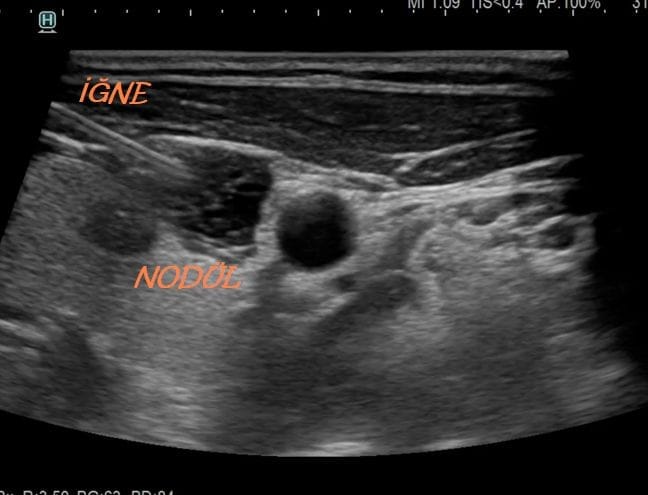

Fine needle biopsy is preferred to examine the content of thyroid nodules. The patient’s skin is first cleaned with an antiseptic solution and local anesthesia may be applied. The doctor inserts a very fine needle into the thyroid nodule under ultrasound guidance. Cell samples are drawn from the nodule with the needle, and if necessary, the procedure can be repeated to obtain multiple samples. The average duration is about half an hour, and it is generally performed without the need for surgery.

The biopsy is performed under ultrasound guidance to ensure accuracy and minimize risk. It is usually quick, well-tolerated, and requires no special preparation. Local anesthesia may be used to reduce discomfort.